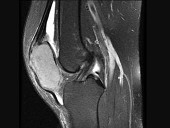

- 单项选择题女,30岁, 膝痛四月余,结合图像, 最可能的诊断是 ( )

A、畸形性骨炎

B、嗜酸肉芽肿

C、成软骨细胞瘤

D、骨囊肿

E、骨巨细胞瘤